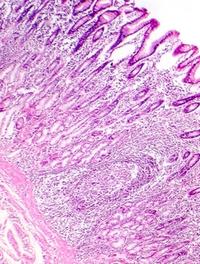

Les complications sont au cœur de la maladie de Crohn (MC) : elles concernent 50 % des patients qui développent des abcès, rétrécissements [...]